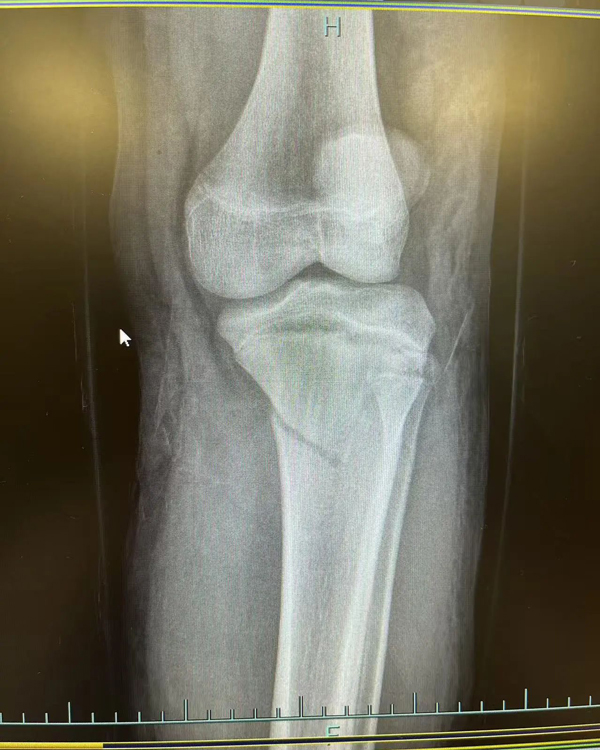

复位前

复位后

进修期间,一段特殊的经历让李刚感触颇深。2月底,一名女性患者因摔伤致左前臂肿痛伴活动受限被送入富阳骨伤医院。通过交流,李刚发现患者竟是家乡同胞,立即用方言安抚其情绪,这位老乡告诉李刚,自己在杭州工作,这次摔伤后先去了别的医院,给出的治疗方案是手术治疗,但听闻富阳中医骨伤医院的中医正骨技术后,慕名而来。经专家团队评估,最终为该患者采用“张氏骨伤疗法”中的手法复位结合杉树皮夹板外固定技术,未开刀便成功修复骨折。